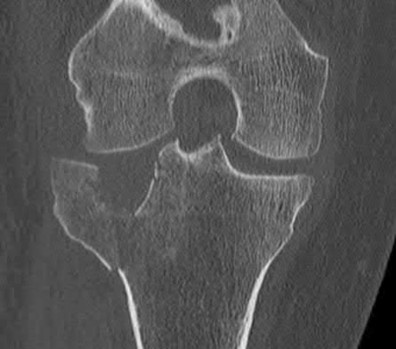

1010) Figures 66a through 66d are the radiographs and CT scans of a 72-year-old woman with osteoporosis who sustained a fall from standing height. She has pain and is unable to bear weight on the right knee. Surgical management is considered. Which of the following best describes the preferred proximal screw fixation construct within a laterally applied buttress plate?

5. 6.5-mm partially threaded cancellous screws Corrent answer: 2

Displaced split depression fractures of the lateral tibial plateau require articular surface elevation, restoration of anatomic plateau width, and sustained elevation of the reduced articular components. This is accomplished by introducing nonlocking lag screws first to compress and narrow the lateral rim thus restoring plateau width. The introduction of locking screws first would disallow compression and accordingly prevent reduction of the lateral rim.

Locking screws are inserted after the lag screws if the bone is osteoporotic to maintain articular elevation. Several biomechanical studies have demonstrated

inferior performance of large implants (6.5-mm screws and 4.5-mm plates) with regard to sustaining joint surface elevation.